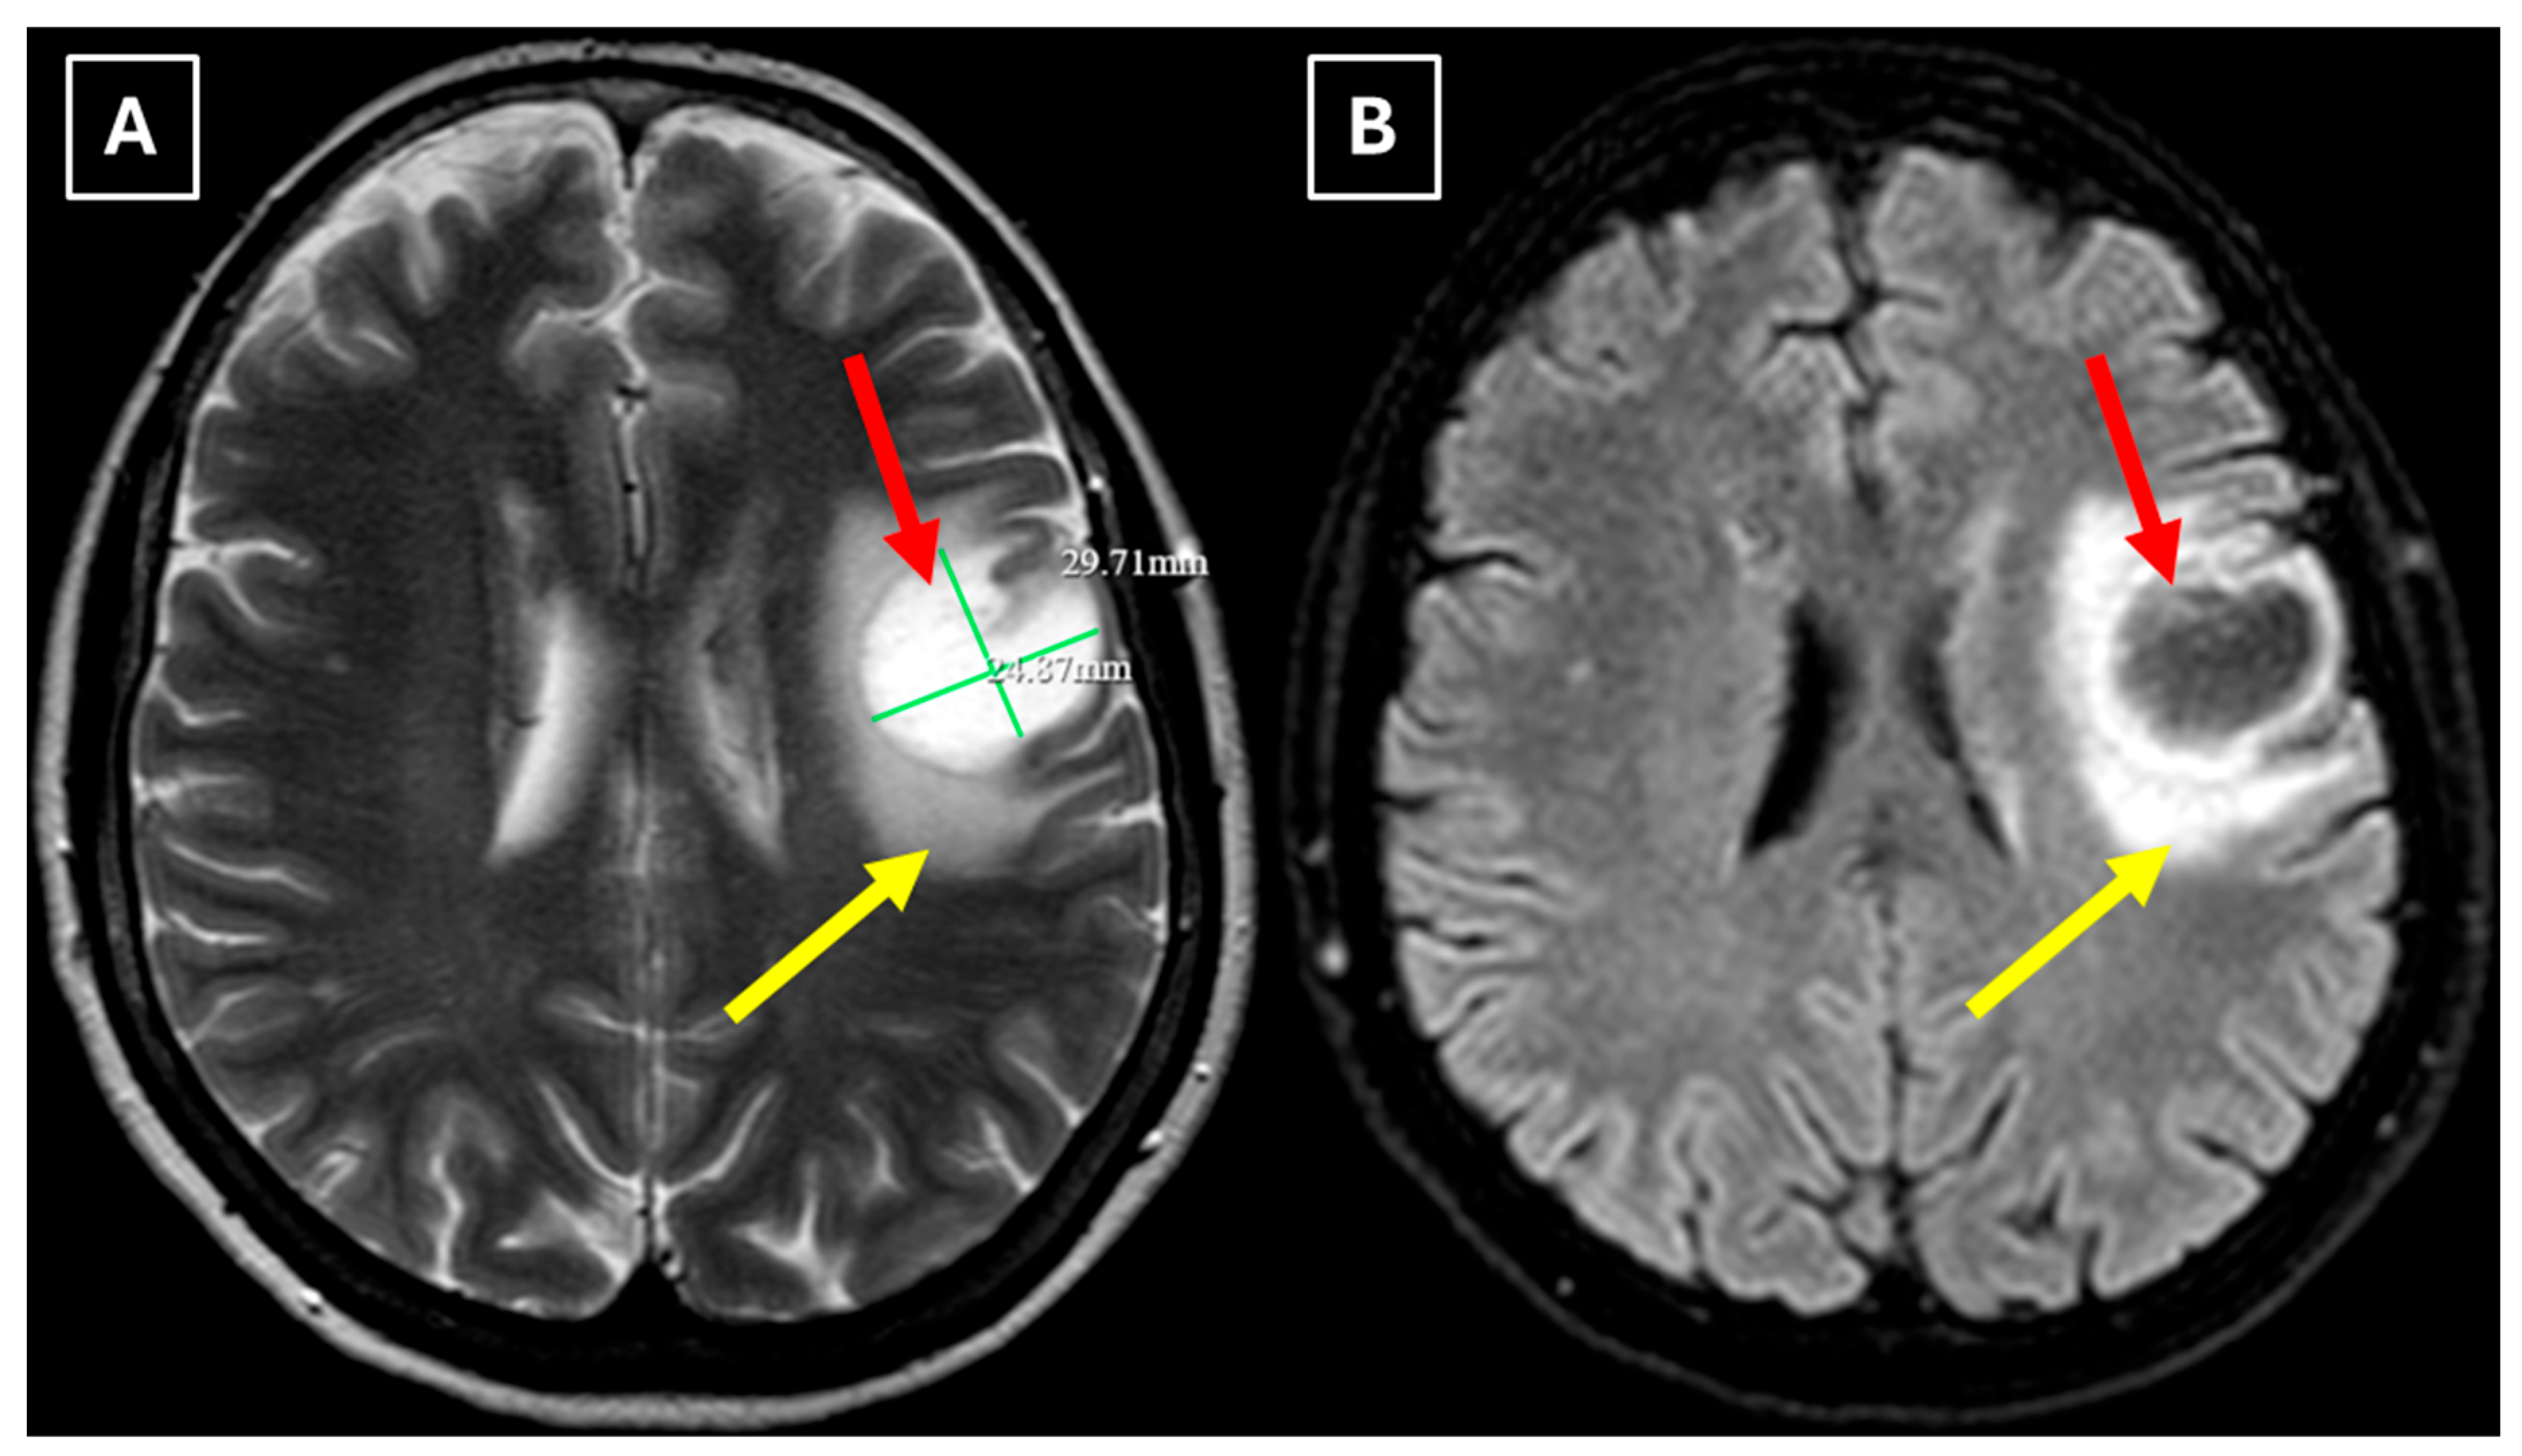

Two months later a follow-up head MRI was performed. It showed a substantial decrease in the volume of the lesion, no mass effect on the surrounding structures, and no perifocal edema (Figure 6 and Figure 7). No other demyelinating lesions were found in the cervical and thoracic spine MRI. The multiple sclerosis board recommended an MRI follow-up after six months as well as a clinical evaluation of the patient.

Figure 6. The 2-month follow-up MRI scan of the brain. In both (A): axial T2W axial sequence and (B): axial FLAIR, the mass has drastically decreased in size and has almost disappeared. A hyperintense demyelination focus can be seen subcortically in the basal parts of the left frontal lobe, which extends more into the white matter and has no mass effect on the surrounding structures. Red arrow—tumefactive demyelinating lesion.

Figure 7. The 2-month follow-up MRI axial scan of the brain. Previously seen peripheral rim-like diffusion restriction is resolved and there is residual minimal vasogenic edema on the axial trace image (A). (B): ADC map. (C): SWI sequence shows no evidence of a left frontal lobe mass but a prominent central traversing vein in the lesion site. (D): T1 postcontrast sequence shows minimal patchy contrast enhancement along the margin of the lesion. Based on the observed changes over the past 2 months, it is most likely that the findings correspond to a demyelinating lesion. Red arrow—tumefactive demyelinating lesion.

Finally, we provide a high-resolution MRI follow-up of two months’ duration showing near-complete regression of the lesion after corticosteroid therapy. The lesion decreased from 37.34 mm × 34.85 mm (AP × LL) to 24.87 mm × 29.71 mm following two weeks of corticosteroid therapy and after almost two months from the first MRI scan to minimal patchy contrast enhancement (Figure 7D). This marked decrease in the size of the lesion gives strong evidence that a demyelinating rather than neoplastic process is present.

Follow-up MRI showed lesion shrinkage after two weeks (Figure 4) and by two months, near-complete lesion regression and resolution of perifocal edema. The radiological course was typical for TDLs and no alternative differential diagnosis appeared reasonable, as both the clinical response to therapy and MRI follow-up strongly supported the demyelinating origin. Thus, biopsy was not performed in this case. In the literature similar cases have been reported where biopsy was avoided, as the disease responded to treatment and imaging findings were consistent with a demyelinating process [27]. Moreover, biopsy of the brain in TDLs carries considerable procedural risks, including seizures and post-operative infections [2]. However, despite the lesion regression after corticosteroid therapy, which was supportive of a TDL diagnosis, the lack of biopsy confirmation represents a limitation in this case and warrants explicit acknowledgment of the risk of misdiagnosis, especially with lesions that have less certain regression.